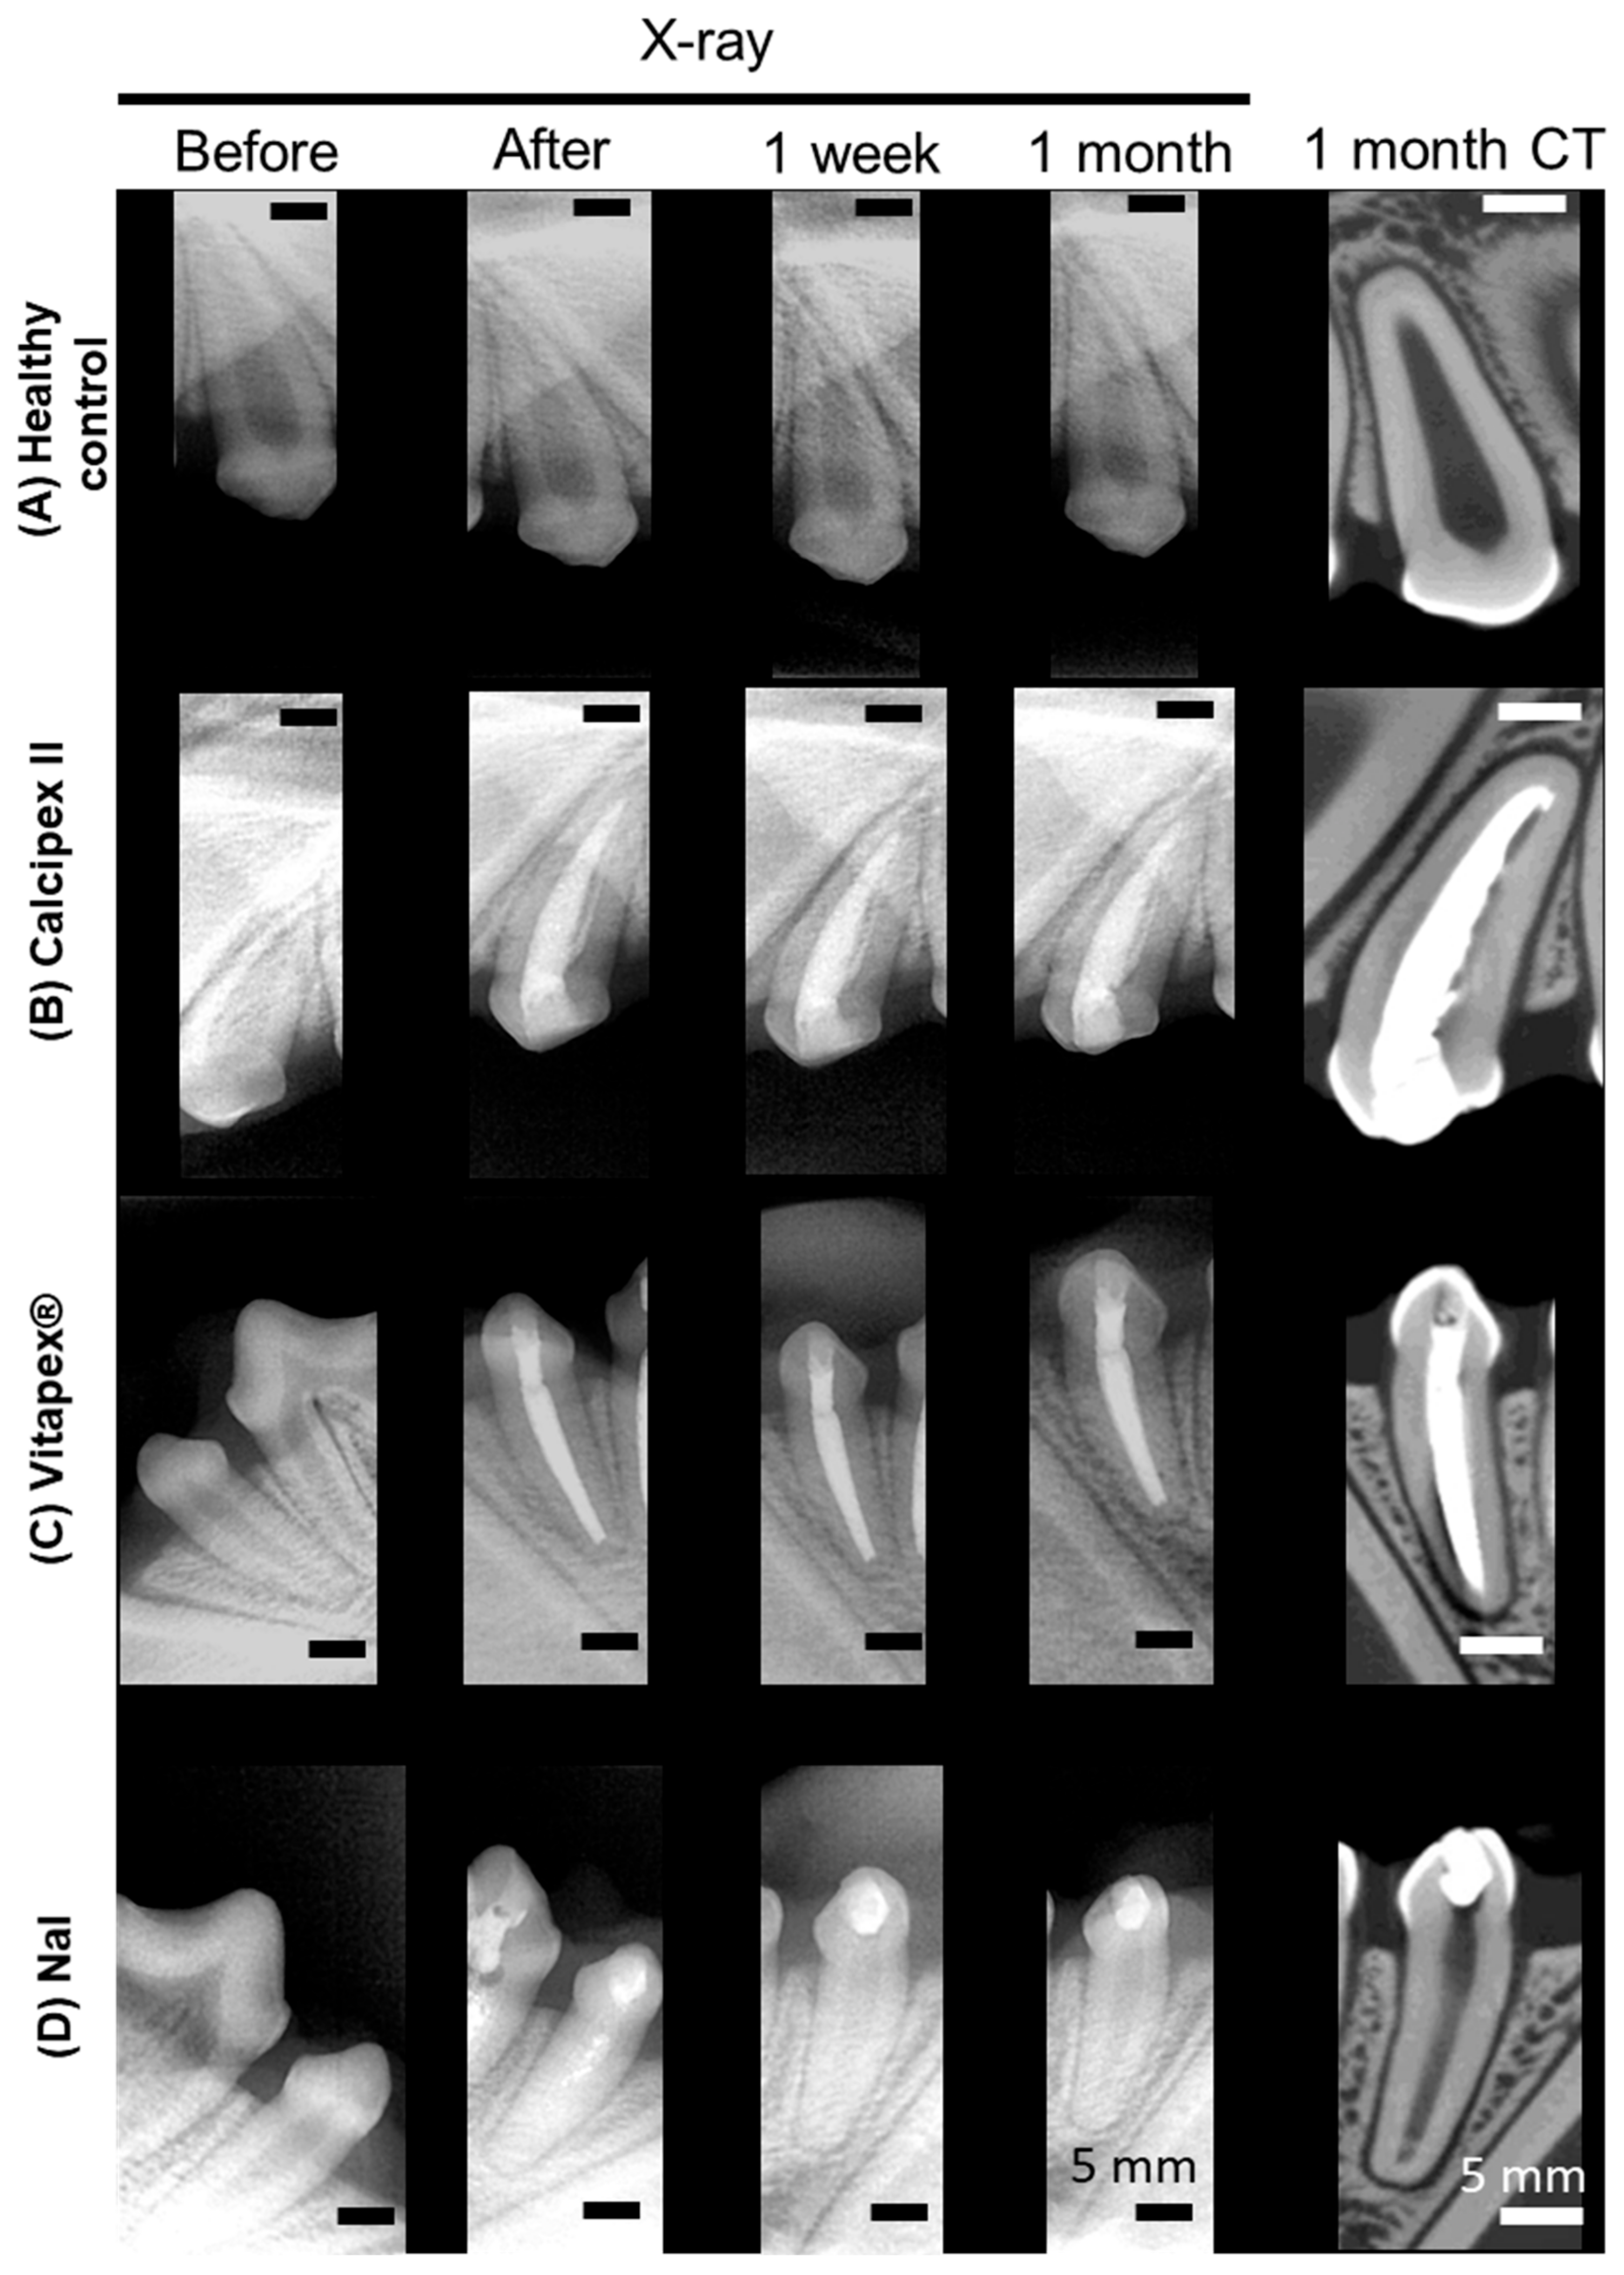

3.1. Radiographic and Micro-Computed Tomographic Evaluation